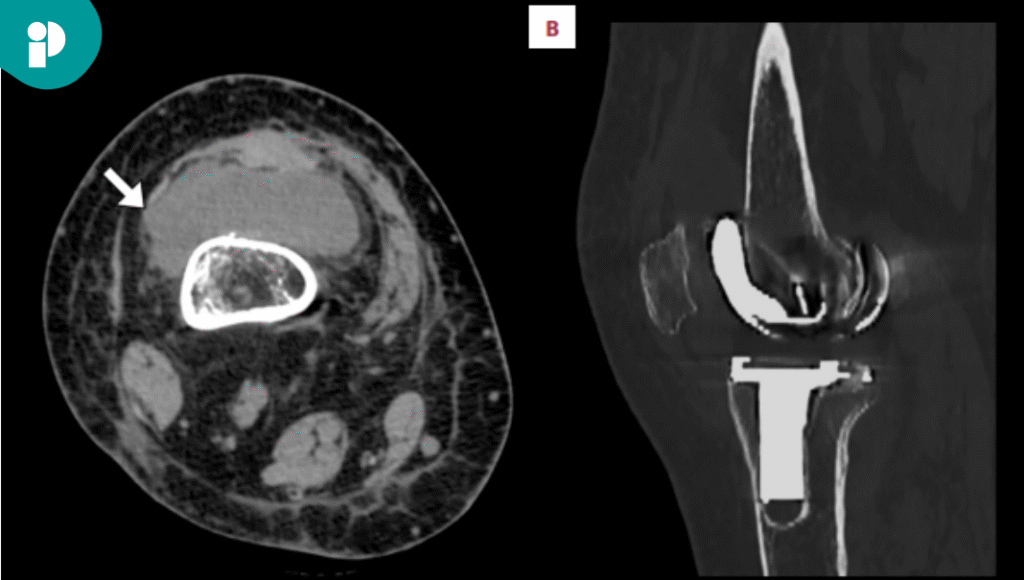

La mujer fue tratada con una combinación de antibióticos intravenosos y orales, específicamente ceftriaxona y cefuroxima, durante un periodo total de 44 días. Además del tratamiento farmacológico, la paciente se sometió a dos cirugías de revisión: una primera etapa de desbridamiento, irrigación y colocación de un espaciador, seguida de una segunda etapa para una revisión completa de la prótesis.